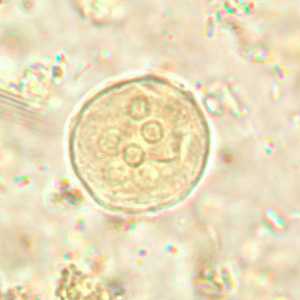

Endolimax nana cysts in concentrated wet mounts.

Figure A: Cyst of E. nana in a direct wet mount, viewed under differential interference contrast (DIC) microscopy.

Figure B: Cyst of E. nana in a direct wet mount stained with iodine.